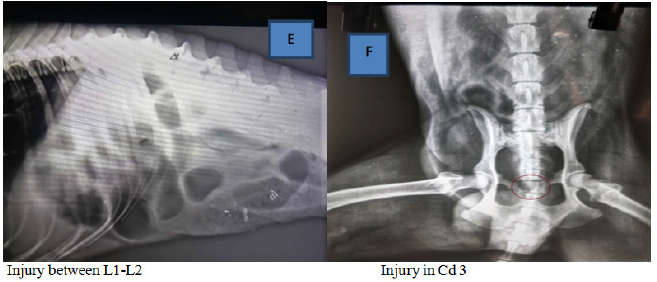

On survey radiography the patient were screened for the vertebral injuries as described in Table 1 and Figures 1A–1F, first case reflecting displacement of L3 in relation to L2, second case showed complete fracture between T12-13, third patient revealed compression in L3, fourth case had fracture of left pubic bone with compression of S3 and fifth and sixth case showed abnormality in both L1-2 and caudal 3 vertebrae. Plain radiography supports findings, formal interpretation for immobilizing the patient appropriately. The failure to adequately immobilize the spine owing to mechanism of injury diagnosis is a pitfall.9

Figure 1A–1F Radiographic investigations.